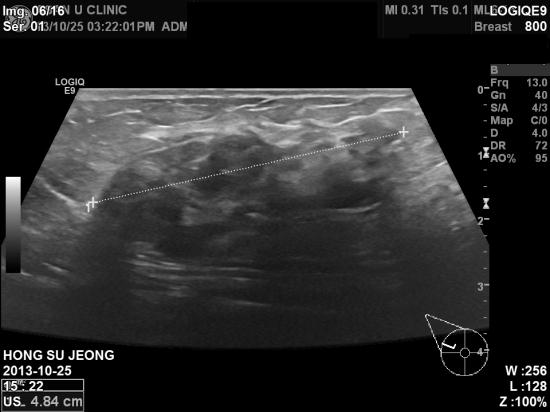

초음파검사상 4.84 cm

혹이있어

, 조직검사결과 침윤성유방암으로

진단되셨습니다